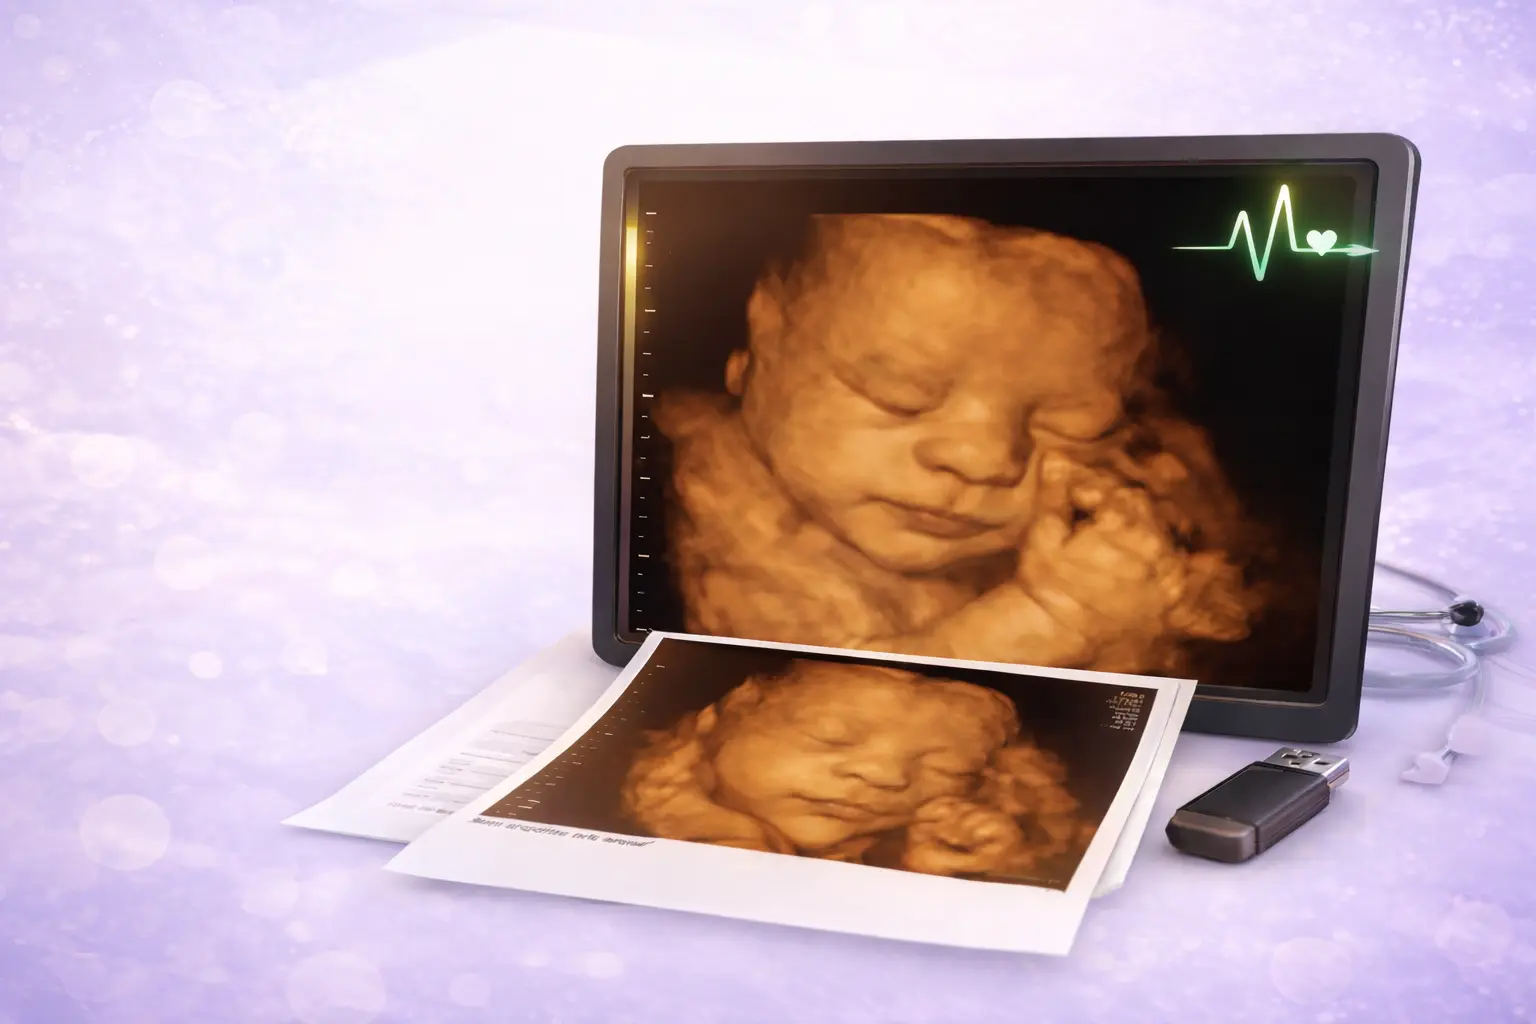

3D & 4D scans - HD Live available (growth scan included)

We use the new GE Voluson Signature 20- with amazing features for 3D/4D scans.

- Receive images of your baby by obtaining 3D and 4D baby scans prior to birth.

- A 40 minute scan including a growth scan and report.

- Two 3D colour images ( 4’ × 6’)

- 3D/4D images/videos on a USB

Watch your baby move in colour and HD live

Acquire detailed images of your baby in the later stages of his or her development.

3D and 4D scans show the best results at 28 weeks or 24 weeks for twin pregnancy.

Our experienced Sonographers are able to provide 3D/4D ultrasound scans from 20 weeks and onwards, however we recommend that you choose the dates suggested above in order to obtain the best results.

- A 3D scan is a still image of a 3 dimensional picture of the baby.

- A 4D scan is a video of a 3 dimensional picture of the baby.

They are performed at the same time and recorded on to a USB.